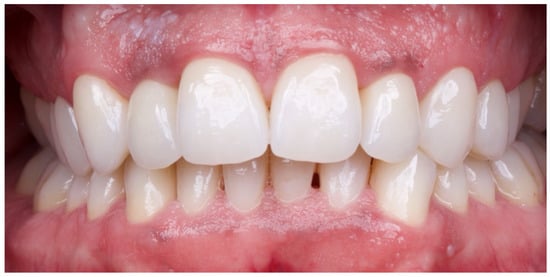

The patient was subsequently enrolled in a structured periodontal and prosthetic maintenance programme, with follow-up evaluations scheduled at four-month intervals to monitor periodontal health, occlusal stability, and the integrity of the prosthetic components (Figure 18, Figure 19 and Figure 20).

Figure 18. Final intraoral image.

Figure 19. Intraoral image at four-year follow-up.

Figure 20. Four-year follow-up radiographic examination.

At the four-year follow-up, clinical evaluation demonstrated stable soft and hard tissues, with no biological or mechanical complications observed throughout the entire follow-up period.

At the four-year follow-up, the clinical situation remained stable and asymptomatic. Periodontal evaluation revealed probing depths within physiological limits, a low plaque index (7%), and minimal bleeding on probing (8%), all consistent with a healthy periodontal environment. Radiographic assessment confirmed the maintenance of alveolar bone levels without signs of resorption. The patient’s reduction in tobacco use and adherence to four-month maintenance therapy intervals likely played a pivotal role in sustaining these outcomes. The four-year follow-up also confirmed the clinical stability of the treatment, both occlusally and periodontally, with a significant improvement in clinical indices and complete patient satisfaction. Masticatory function remained effective, the deep bite was corrected, and the interincisal diastema was successfully closed, resulting in a harmonious and stable aesthetic outcome. The final decision to fabricate individual crowns was justified by the favourable tissue response and the occlusal stability achieved.